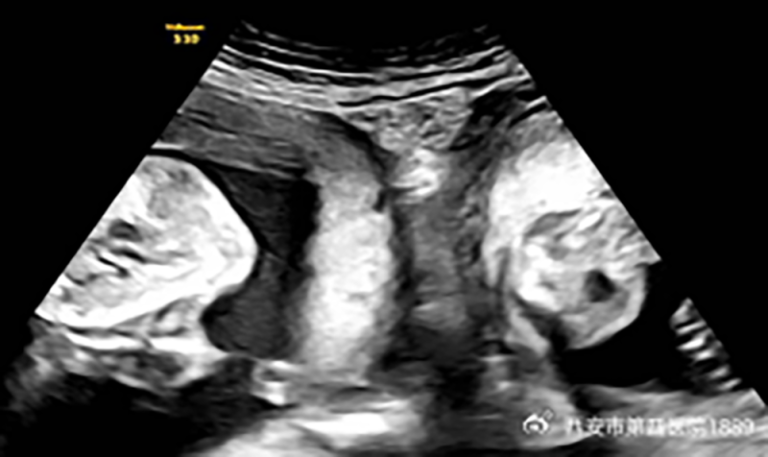

But in January, Li became pregnant again and discovered during an early ultrasound that she was expecting not just one child but twins – one in each womb.

After “close and strict” medical monitoring, she “successfully” gave birth to a boy weighing 7 pounds, 19 ounces and a girl weighing 5 pounds, 30 ounces, the hospital said.